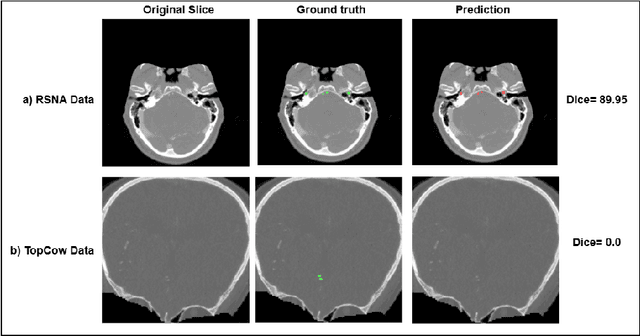

Abstract:The clinical deployment of deep learning models in medical imaging is severely hindered by domain shift. This challenge, where a high-performing model fails catastrophically on external datasets, is a critical barrier to trustworthy AI. Addressing this requires moving beyond simple performance metrics toward deeper understanding, making Explainable AI (XAI) an essential diagnostic tool in medical image analysis. We present a rigorous, two-phase approach to diagnose the generalization failure of state-of-the-art State-Space Models (SSMs), specifically UMamaba, applied to cerebrovascular segmentation. We first established a quantifiable domain gap between our Source (RSNA CTA Aneurysm) and Target (TopCoW Circle of Willis CT) datasets, noting significant differences in Z-resolution and background noise. The model's Dice score subsequently plummeted from 0.8604 (Source) to 0.2902 (Target). In the second phase, which is our core contribution, we utilized Seg-XRes-CAM to diagnose the cause of this failure. We quantified the model's focus by measuring the overlap between its attention maps and the Ground Truth segmentations, and between its attention maps and its own Prediction Mask. Our analysis proves the model failed to generalize because its attention mechanism abandoned true anatomical features in the Target domain. Quantitative metrics confirm the model's focus shifted away from the Ground Truth vessels (IoU~0.101 at 0.3 threshold) while still aligning with its own wrong predictions (IoU~0.282 at 0.3 threshold). This demonstrates the model learned spurious correlations, confirming XAI is a powerful diagnostic tool for identifying dataset bias in emerging architectures.